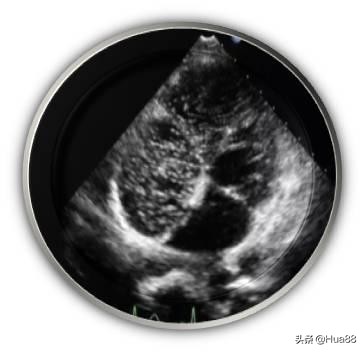

相关检查 医生如怀疑或排查患者是否存在卵圆孔未闭,通常会完善以下检查。由于超声心动图可以直观地显示房间隔解剖结构及心脏内血流分流情况,因此超声心动图是卵圆孔未闭的最 佳诊断检查。 临床上常用的超声心动图包括经胸超声心动图(TTE)、经食管超声心动图(TEE)和经颅多普勒超声声学 造影(cTCD)。 经胸超声心动图(TTE) 性价比高,操作简单、无痛苦,但该检查会受到肥胖和肺气过多等因素的干扰,检出率不高,且难以准确测 量未闭的卵圆孔大小,一般应用于儿童及部分成年人。 经胸超声心动图声学造影(cTTE)可以提高检出率,了解患者有无心脏内血液异常分流。操作时需要静脉注 射声学造影剂。 经食管超声心动图(TEE) 是诊断卵圆孔未闭的“金标准”和首选方法。该检查可以指导医生对卵圆孔未闭进行分类,从而指导治疗。 该检查属于半创伤性检查,操作过程中患者比较痛苦,类似于胃镜检查,插管会造成患者恶心、呕吐等不 适。检查前后患者须禁食、禁水。 经食管超声心动图声学造影(cTEE)亦可用于判断心脏内血液异常分流情况。 此外,三维经食管超声心动图(三维TEE)能够为二维TEE图像提供有力补充,帮助医生了解实时未闭卵圆 孔的状态,更有利于指导治疗。 经颅多普勒超声声学造影(cTCD) 简单、无创、安全。检查心脏内血液有无分流的一种常用方法,但是不能定性诊断卵圆孔未闭。作为卵圆孔 未闭筛查的一种方法,通常需要进一步进行经胸超声心动图(TTE)、经食管超声心动图(TEE)等检查作 为补充。 心导管检查、对比分析双源CT冠状动脉成像和心脏磁共振成像(MRI)可以发现卵圆孔未闭,但费用较高, 敏感性相对较差,临床较为少用。

右心声学造影+发泡实验